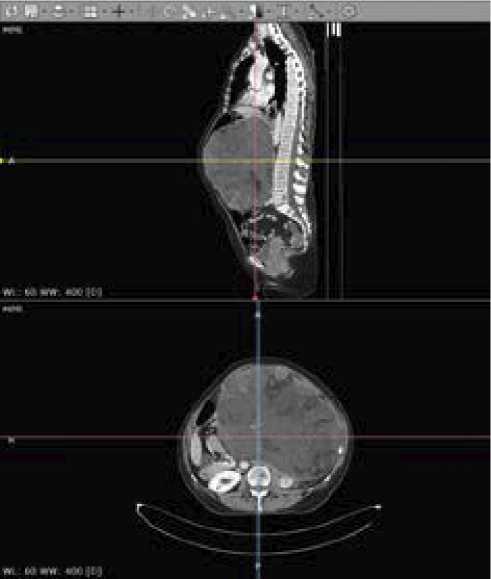

КТ-сканирование с контрастированием за 3 дня до операции выявило,что в центральных и левых отделах брюшной полости есть опухоль размерами 243 × 183 × 244 мм, структура неоднородная — кистозно- солидная с жировыми включениями (рис. 1 и 2). Петли тонкой кишки оттеснены вправо, левая половина поперечной и нисходящая часть ободочной кишки компримированы между новообразованием и передней брюшной стенкой, желудок и поджелудочная железа оттеснены вправо, селезенка — поддиафрагмально. Левая почка деформирована новообразованием, смещена кзади и медиально. Сосудистая ножка почки компримирована, почечная артерия прослеживается, почечная вена четко не дифференцируется. Кортико-медуллярная дифференциация почки сохранена, в прилежащей к опухоли паренхиме почки определяются участки гипоперфузии (компрессионные изменения).

Рисунок 1. КТ-сканы до операции

Figure 1. CT scans before surgery

Рисунок 2. КТ-сканы до операции

Figure 2. CT scans before surgery